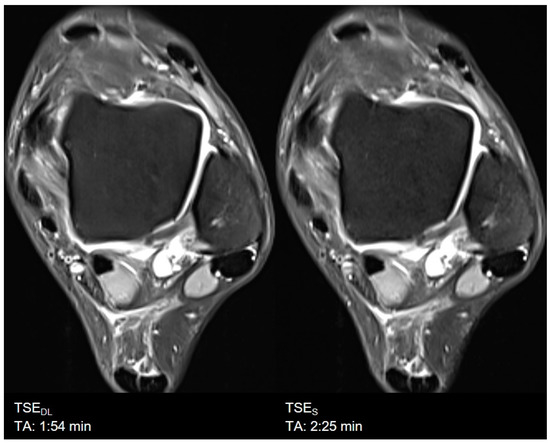

| Ankle | TSES | TSE PD FS | axial | 2:25 | 150 | 0.4 × 0.4 × 3.0 | 1 | 1 | 2 | 3340 | 17 | 150 | 90 | 17.1 |

| sagittal | 1:47 | 160 | 0.2 × 0.2 × 3.0 | 1 | 1 | 3 | 3000 | 32 | 150 | 100 | 15.9 | |||

| TSEDL | TSE PD FS | axial | 1:54 | 150 | 0.4 × 0.4 × 3.0 | 1 | 1 | 3 | 3000 | 17 | 150 | 90 | 16.9 | |

| sagittal | 1:45 | 160 | 0.4 × 0.4 × 3.0 | 1 | 1 | 3 | 3000 | 31 | 150 | 100 | 15.7 | |||